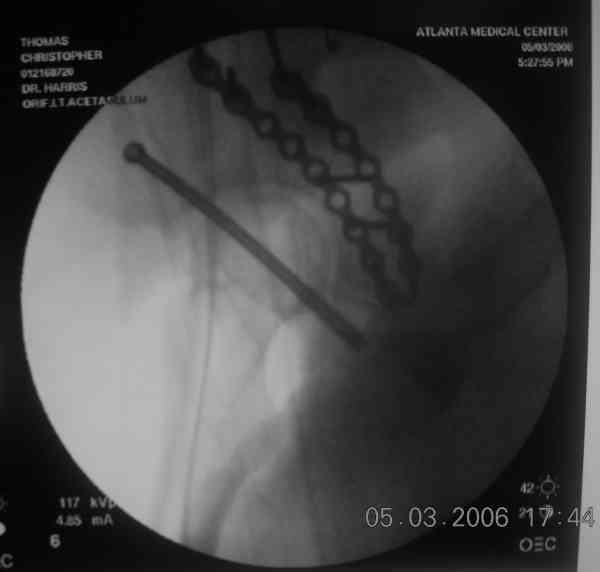

For this fracture pattern, I have had good luck with fluoro guided anterior column screw first.

pt supine helps get the best fluoro images. then cut the guide wire below the skin and leave it in place along with the anterior column screw. staple the small incision closed and cover with ioban. then reposition, remove ioban, reprep/drape pt in lateral decub for KL approach.

sometimes the anterior column screw needs to be backed out to help get the best reduction of posterior column. with guide wire in place this is fairly easy, the fracture will rotate around the wire, and the anterior column screw can be readvanced with confidence it is within bone. I have intra-op photos on office computer if interested.

the case that I found is a 20yo male, MCC. his AP pelvis shows an interesting position of his bladder. it is pushed aside by a hematoma from SGA injury. we did a limited lateral window approach for the anterior column first, pt bumped up/supine. then closed and repositioned for KL. I could not find intra-op photos of cases when we did only a small incision for the AC screw (but they do exist!!). the lateral window is available for reduction assessment if a KL approach is being used. in the lateral position this window is available. the prone position definitely takes pressure off of the post column and facilitates reduction. in the lateral position a schantz pin in the ischial tub +/- bone hook in sciatic notch helps with PC reduction. the lateral position also gives better airway access for anesthesia. airway problems are rare, but prone position seems to be a bit more of a challenge to exchange the tube, or reintubate altogether. just something further to debate!